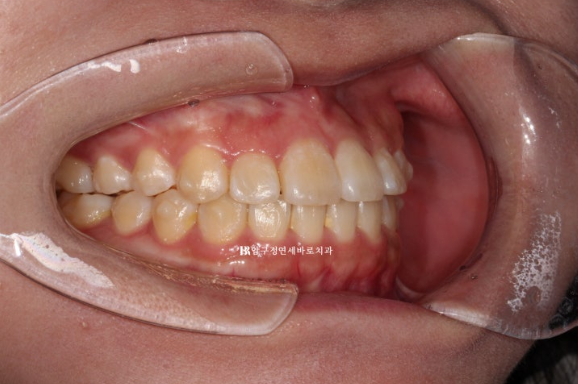

24.01

들려있던 일자로 내려오면서 치아가 처음보다 약간 길어보이네요.